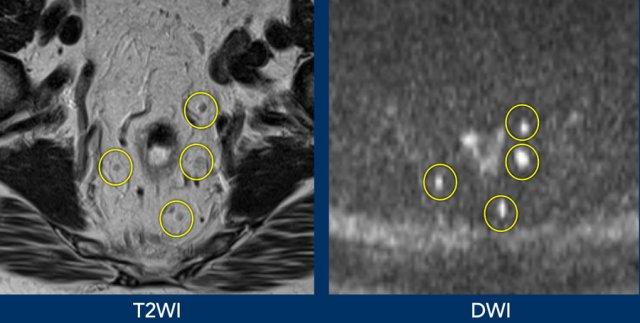

Vai trò của DWI trong việc phát hiện khối u còn sót lại

Hình ảnh khuếch tán (DWI) làm nổi bật mô có mật độ tế bào cao, nơi sự di chuyển của nước ngoại bào bị hạn chế.

Giá trị chính của nó nằm ở việc phát hiện khối u còn sót lại trong tình trạng dày thành xơ hóa khu trú (một phần dạng vòng nhẫn) tại vị trí khối u đã được điều trị.

Trong các trường hợp có khối u còn sót lại, tín hiệu cao thường được thấy ở bờ trong của mô xơ trên DWI giá trị b cao, với tín hiệu thấp tương ứng trên bản đồ ADC.

Ví dụ về Hình ảnh

- Hình ảnh T2-weighted phân giai đoạn ban đầu và phân giai đoạn lại cho thấy vùng nền khối u chủ yếu xơ hóa với tín hiệu không đồng nhất nhỏ (mrTRG 3) sau hóa xạ trị.

- Hình ảnh DWI tái giai đoạn cho thấy vùng tín hiệu cao khu trú tại bờ trong của xơ hóa, với tín hiệu ADC thấp, cho thấy sự khuếch tán bị hạn chế.

- Mô bệnh học xác nhận đây là phần mô u còn sót lại nhỏ (ypT2)

Hạch bạch huyết, giống như tất cả các mô bạch huyết (ví dụ: lách), có cấu trúc tế bào dày đặc, dẫn đến khuếch tán bị hạn chế và tín hiệu DWI cao.

DWI có thể tăng cường khả năng phát hiện hạch bạch huyết, đặc biệt ở những vùng mà các hạch dễ bị bỏ sót, chẳng hạn như vùng chậu hông trong.

Hạn chế:DWI không thể phân biệt đặc điểm hạch bạch huyết—cả hạch lành tính và hạch di căn đều cho tín hiệu cao.

Ví dụ Hình ảnh

- Hình ảnh hạch bạch huyết được cải thiện trên DWI so với hình ảnh trọng số T2.

- DWI không hữu ích trong việc đánh giá nguy cơ ác tính ở các hạch này.